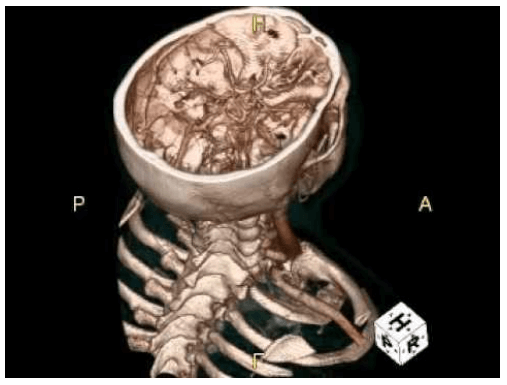

3D CT scan

Three dimensional CT (3D CT) is essentially a method of surface rendition of anatomy by means of a special computer software.